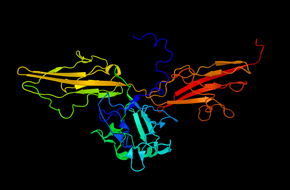

充分利用我们的结构生物学服务组合,这包括重组蛋白表达和蛋白质晶体学,以及RNAi靶点验证服务。